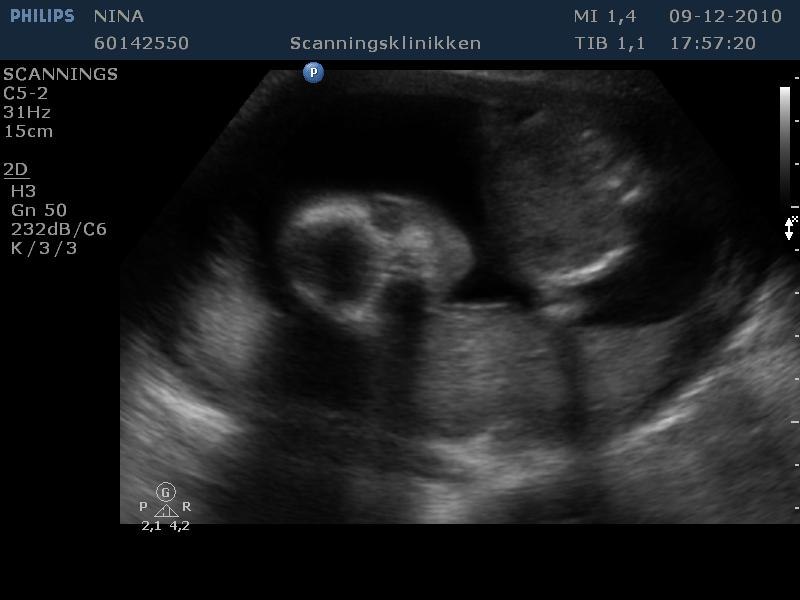

Billede 2: Nakkefold scanning